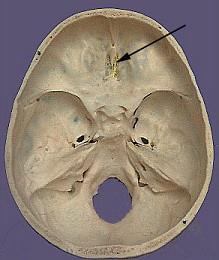

问题 如图箭头所示为哪支脑神经 ( )

选项 A、Ⅴ B、Ⅰ C、Ⅲ D、Ⅳ E、Ⅱ 一、单项选择题

答案 B